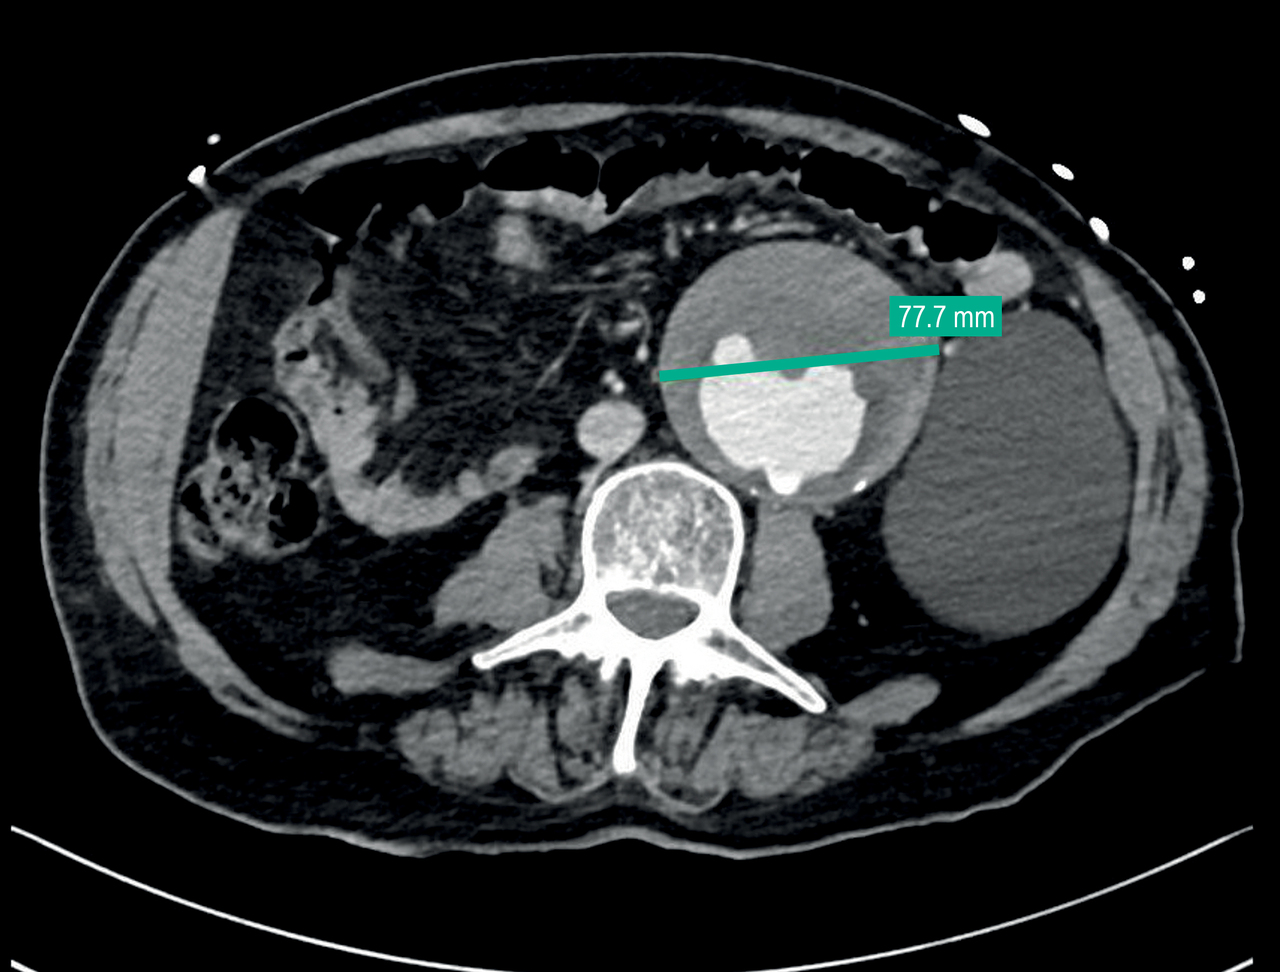

Le scanner objective :

• un hématome intramural de l’aorte thoracique et abdominale étendu aux troncs supra-aortiques avec fuite de produit de contraste dans la paroi de l’aorte thoracique au temps artériel avec hémopéricarde ;

• une importante dilatation anévrismale de l’aorte thoracique (54 mm de diamètre maximal) et abdominale (78 mm de diamètre maximal) ;

• une densification de la graisse péri-aortique au niveau de son hiatus et juste en aval, faisant suspecter une fissuration.